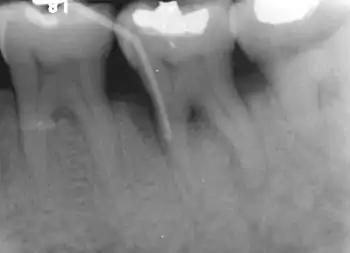

Nabers probe is used to check for furcation involvement clinically. Recently, cone beam computerised technology (CBCT) has also be used to detect furcation.[5] Periapical and interproximal intraoral radiographs can help diagnosing and locating the furcation.